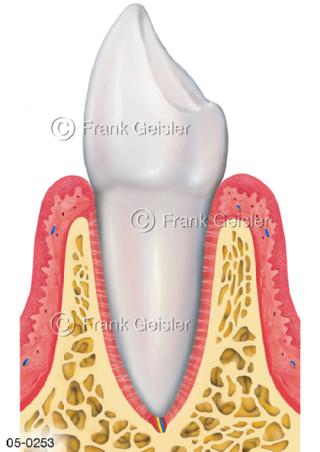

Bildergalerie Skelettsystem

Bilder zum Skelettsystem zeigen die Stützstruktur des menschlichen Körpers, die Knochen, eine besonders harte Form des Bindegewebes und Stützgewebes, welche das menschliche Skelett bildet, die Knochen des Stammes, der Extremitäten sowie der Gelenke